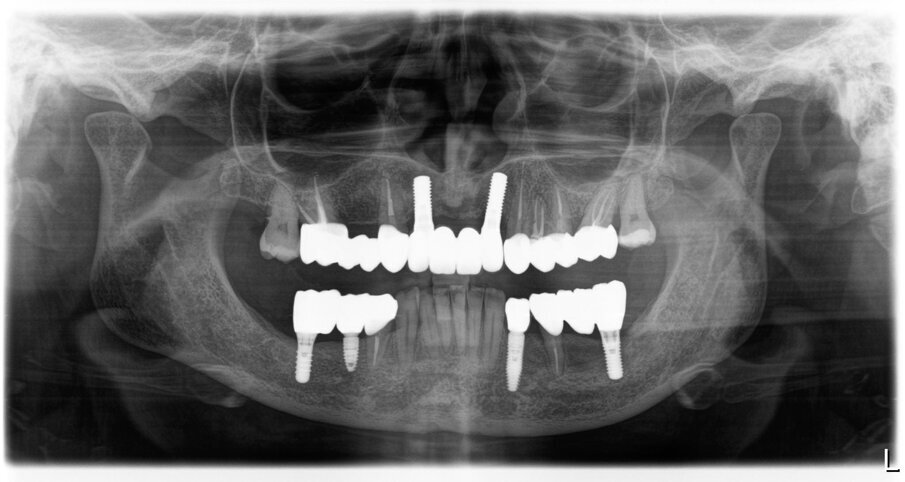

Nell’arcata inferiore dopo il trattamento parodontale abbiamo mantenuto inalterato il V° sestante provvedendo alla rimozione del 3.7 mesio-inclinato con sondaggio e mobilità difficilmente recuperabili e sostituendolo con un impianto. La scelta implantare poco convenzionale ha previsto per la sostituzione bilaterale dei diatorici con impianti in titanio di differente forma e connessione, inserendo bone level (BL) sui premolari e tissue level (TL) sui molari con una protesizzazione mista. La scelta del BL o del TL era rivolta a un aspetto estetico sui premolari e di maggior rispetto tessutale sui molari. Durante le fasi di prova (Fig. 41) si valutano le compressioni dei tragitti transmucosi (Fig. 42), gli eventuali precontatti, si finalizzano le forme e si rileva nuovamente il colore secondo la tecnica di depolarizzazione (Fig. 43). L’appuntamento successivo sancisce l’ottimizzazione dei restauri (Figg. 44, 45). Dopo il posizionamento definitivo dei restauri protesici e l’ottimizzazione dei contatti (Fig. 46) viene nuovamente registrato l’equilibrio di masticazione tramite l’uso del sincronogiografo che registra le forze muscolari confrontando i valori registrati dal momento iniziale pre-trattamento a quello con i provvisori e infine alla stabilizzazione finale, così che nel tempo si possa aver traccia dell’adattamento realizzato (Fig. 47). Il recupero funzionale ed estetico (Figg. 48, 49) rappresentano il traguardo dopo un lungo percorso. Il condizionamento della paziente ha rappresentato un ostacolo nelle libere scelte cliniche segnando di conseguenza l’intero percorso. L’aspetto psicologico ha giocato un ruolo importante nella realizzazione del piano di trattamento, la malattia precedente e il lungo periodo di provvisorizzazione ha arrecato nella paziente un forte disagio. Talvolta quest’aspetto induce il clinico a fare dei compromessi procedurali e anche noi abbiamo cercato di ottimizzare una riabilitazione estetico funzionale correndo dei rischi procedurali a fronte di una richiesta conservativa e talvolta riduttiva nelle procedure chirurgiche. A oggi il follow-up e i controlli di igiene e di verifica della funzione è cadenzato e rigorosamente rispettato dalla paziente. A 5 anni non sono stati evidenziati problemi dei materiali impiegati né tantomeno funzionali (Figg. 50, 51).

Fig. 50_Radiografia iniziale

Fig. 51_Radiografia a 5 anni dalla consegna del lavoro. Ai follow-up vengono eseguite annualmente delle rx endorali centrate, e alla necessita viene ripetuta un’opt.

Il trattamento è durato 12 mesi. Non è stata anticipata alcuna procedura e abbiamo atteso i giusti tempi nella guarigione dei tessuti molli e duri attendendo sei mesi dall’inserimento dei due impianti in regione incisiva e dopo debito controllo radiografico. La giusta maturazione delle procedure attuate ha consentito una stabilità che ancora oggi a distanza di 5 anni rimane inalterata con piena soddisfazione personale. Inoltre la scolarizzazione della paziente nel mantenimento domiciliare ha creato un rapporto di benessere e di fiducia che reputiamo indispensabili nel follow-up a lungo termine. Non abbiamo riscontrato alcuna differenza significativa tra gli impianti in Zirconia e quelli in titanio dal punto di vista dei controlli radiografici e della qualità dei tessuti. In regione frontale l’estetica rosa è esaltata dalla trasparenza favorevole di collarini bianchi che non opacizzano la visione in trasparenza. Reputiamo l’approccio digitale come un forte ausilio tecnologico nelle scelte delle procedure e dei materiali oltre che un’eccellente strumento di comunicazione col paziente che contrariamente a noi è spesso disorientato verso le nostre procedure per il dubbio del risultato.